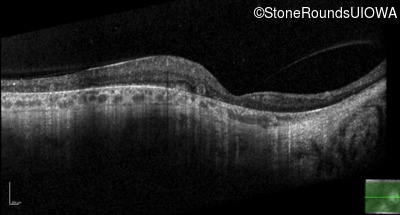

Optical Coherence Tomography - Left - 20/40 sc

Exemplar / OCT Stack

OCT Stack